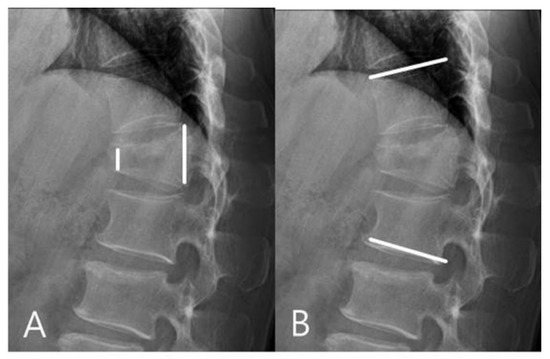

For the mono group, the preoperative mean RKA was 21.56°, and the postoperative mean RKA was 8.13°. The mean correction angle was 13.43° (correction rate 62.31%). The RKA angle decreased from 8.13° to 11.18° (correction loss: 14.18%) in late follow-up. For the poly group, the preoperative mean RKA was 23.18°, and the postoperative mean sagittal plane kyphosis was 11.09°. The mean correction angle was 12.09° (correction rate 52.17%).The RKA decreased from 11.09° to 18.83° (correction loss: 33.42%) in late follow-up. The mono-axial pedicle screw fixation had a better correction rate and reduced the risks of correction loss versus the poly-axial pedicle screw fixation (Figure 3 and Figure 4).

Figure 4.

(A) 45-year-old male patient with L1 burst fracture was treated by poly-axial pedicle screw fixation. (B) Postoperative imaging showed a mild correction of anterior body height and kyphosis. (C) Final follow-up imaging showed correction loss.